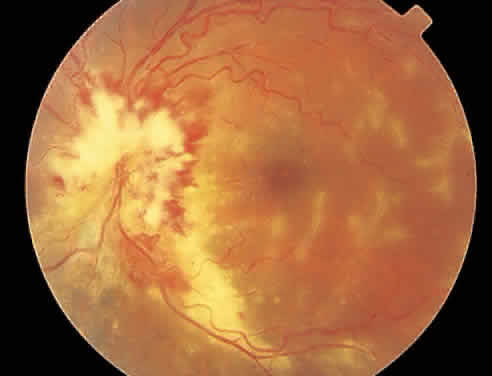

The hallmark lesion of CMV retinitis is a necrotizing, full-thickness retinitis that results in retinal cell destruction. CMV often initially affects retinal tissue adjacent to major retinal blood vessels or the optic disc (Fig. 1). This is consistent with the concept that the virus is spread to the retina hematogenously. In most cases, the pattern of infection is classic and distinctive, making clinical diagnosis straightforward. The area of active retinitis has a granular, dirty-white appearance. As the virus attacks the endothelial cells of blood vessels, hemorrhage is common. Advancement in the retinitis by both direct cell-to-cell transmission as well as spread by way of adjacent satellite lesions can be seen. Except for cases in which retinitis is acute, it is common to see areas of healed retinitis beside areas of active necrosis. Areas of burned-out necrosis show absence of any retinal tissue, whereas the underlying retinal pigment epithelium assumes a “salt and pepper” appearance. CMV retinitis can present initially as either large areas of retinal necrosis with hemorrhage or one or more small, focal areas of retinal whitening.1,12,14 These small, focal lesions may on occasion be confused with cotton-wool spots or lesions of toxoplasmosis.5,27 Unlike cotton-wool spots, focal areas of CMV may appear outside the posterior pole. These early, focal infiltrates of CMV may not be associated with retinal hemorrhages or vitreous cells.

Over a course that usually spans weeks, infiltrates of CMV tend to assume two different patterns of clinical disease.11,12 The first pattern is called hemorrhagic and is characterized by broad geographic zones of retinal whitening. These large, geographic lesions are usually in close proximity to a major retinal blood vessel or the optic nerve. Satellite lesions are common. When the retinal necrosis associated with CMV retinitis becomes widespread, it is almost invariably associated with retinal hemorrhages. Although the border between necrotic and unaffected retina is sharply demarcated, the border itself appears irregular and jagged. Exudation into the retina or subretinal space may be seen, adding to the granular appearance of the retinitis. Juxtaposition of large zones of white, granular necrosis with those of red retinal hemorrhage has led this appearance of CMV retinitis to be described as either “pizza-pie” or “cheese and ketchup.” The retinal blood vessels, both arteries and veins, in the areas of necrosis commonly appear sheathed, secondary to a vasculitis. As a consequence, secondary retinal vascular occlusions, especially branch retinal vein obstructions, may occur in the course of CMV retinitis. Immune-mediated vascular damage may play a role in the vasculitis.12 Central healing of these lesions will occur as the infection progresses. Avasculitis resembling “frosted branch angiitis” hasbeen reported (Fig. 2).28 A second pattern of CMVretinitis has been labeled “granular” or “brushfireborder.” In this appearance, the focal granular infiltrates enlarge slowly across a line, leaving ever-increasing areas of destroyed retina and atrophic retinal pigment epithelium behind. Hemorrhages and vitreous cells are a less prominent feature. There appears to be direct cell-to-cell transfer of infected virions in this pattern of infection (Figs. 3 and 4). The brushfire border is commonly seen in CMV retinitis lesions anterior to the equator (Fig. 5). The significance, if any, of these two clinical patterns of CMV retinitis is not known, and, in some eyes, both patterns of disease can be seen simultaneously or in sequence. Progression of retinitis has been defined in clinical trials as movement of a lesion border at least 750 μm along a front that is 750 μm or more in length, development of a new CMV lesion in a previously involved eye or in the uninvolved fellow eye of a patient with baseline unilateral disease.29 Without treatment or improvement in the host's immune system, CMV retinitis is a relentless, slowly progressive infection resulting in blindness caused by total retinal necrosis, retinal detachment, or optic nerve involvement, in any combination.